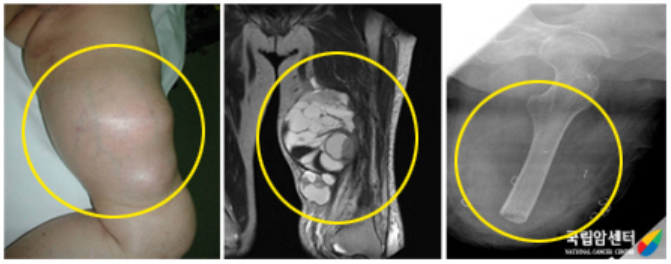

[ 왼쪽 무릎관절 주위에 발생된 활막육종 환자의 사진 ]

이 종양은 진행이 느리기는 하지만 결국 폐에 전이됩니다. 종양의 부분 절제나 주위 조직을 불충분하게 절제한 경우 수개월에서 1~2년 이내에 대부분이 재발됩니다. 원발 부위 재발이 없는 경우나 절단 치료 후에도 종종 폐에 전이되는 것으로 보아 활막 육종의 전이는 비교적 초기에 일어난다고 생각할 수 있습니다. 따라서 활막 육종은 광범위 절제술 후 항암제 투여 및 방사선 치료가 재발 및 전이를 억제하는 데 도움이 될 수 있습니다.

방사선상으로는 관절 주위 연부조직에 원형 또는 타원형의 음영을 볼 수 있으며, 간혹 종양 내에 석회화를 나타내기도 합니다.